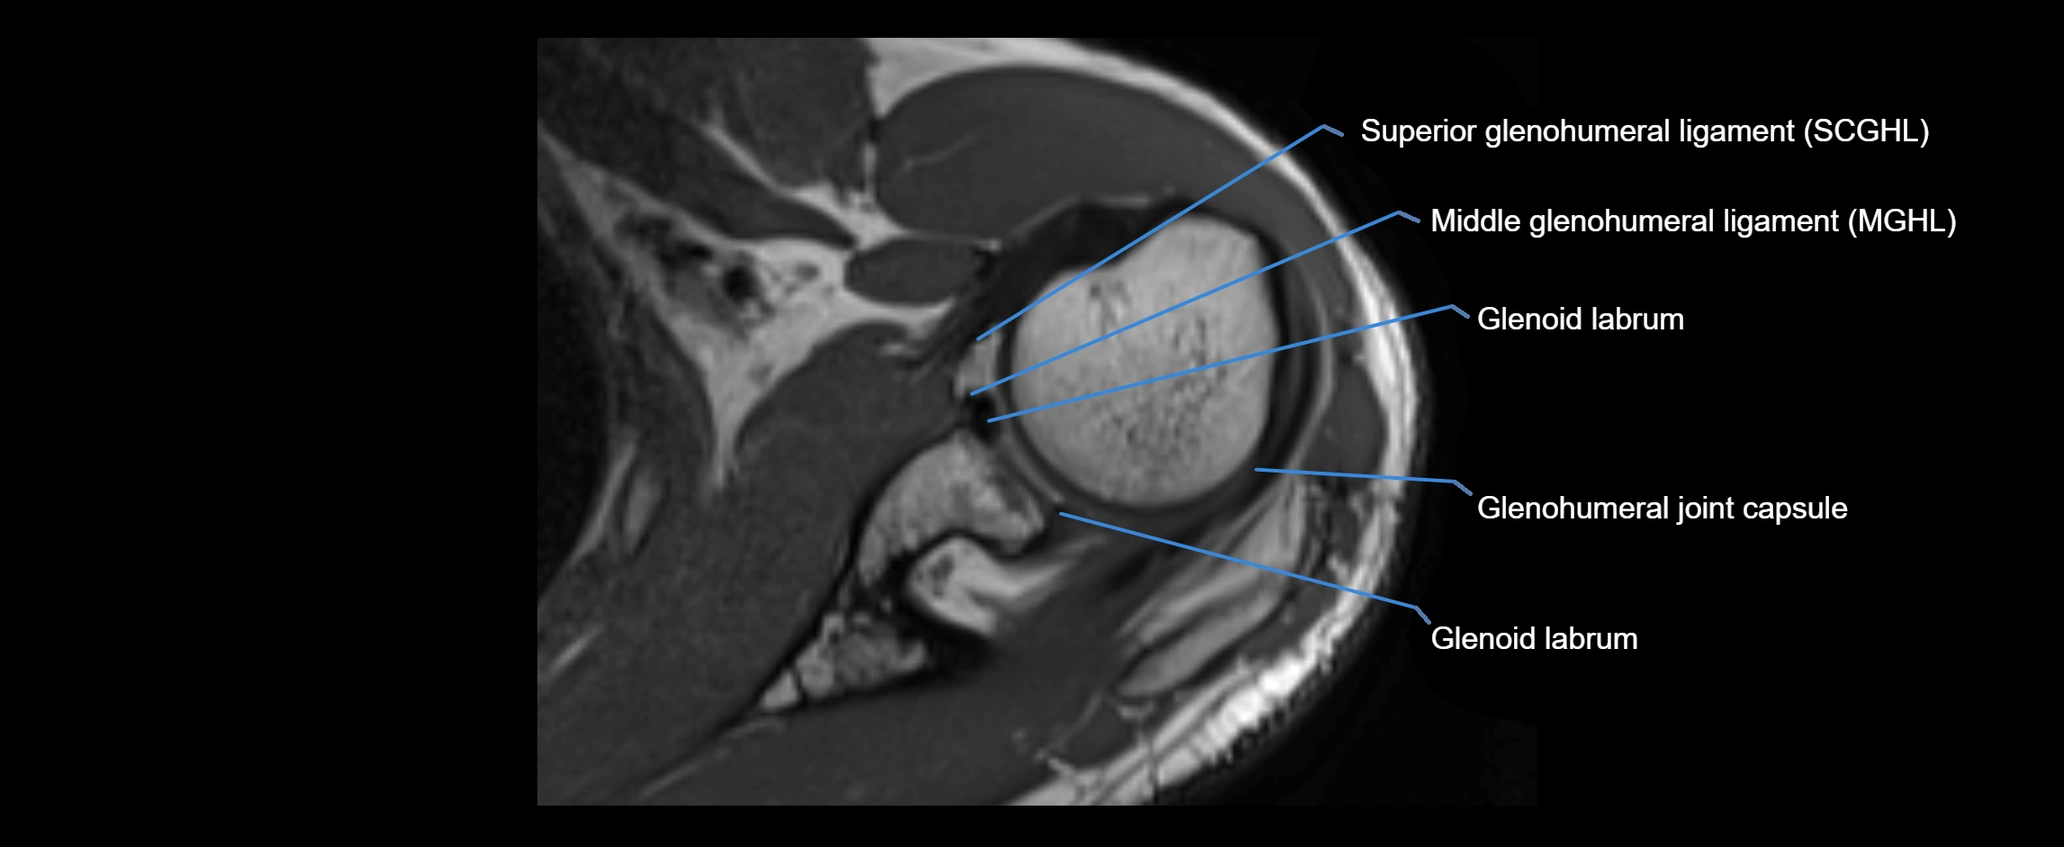

MRI images

image

MRI Appearance

• Proton Density Fat-Saturated (PD FS):

• Normal ligament: Low signal, uniform thickness.

• Partial tear or sprain: Bright signal or contour irregularity.

• Complete tear: Clear discontinuity with bright signal gap and joint effusion.

• Excellent for assessing joint capsule, coracoclavicular ligaments, and periarticular edema.